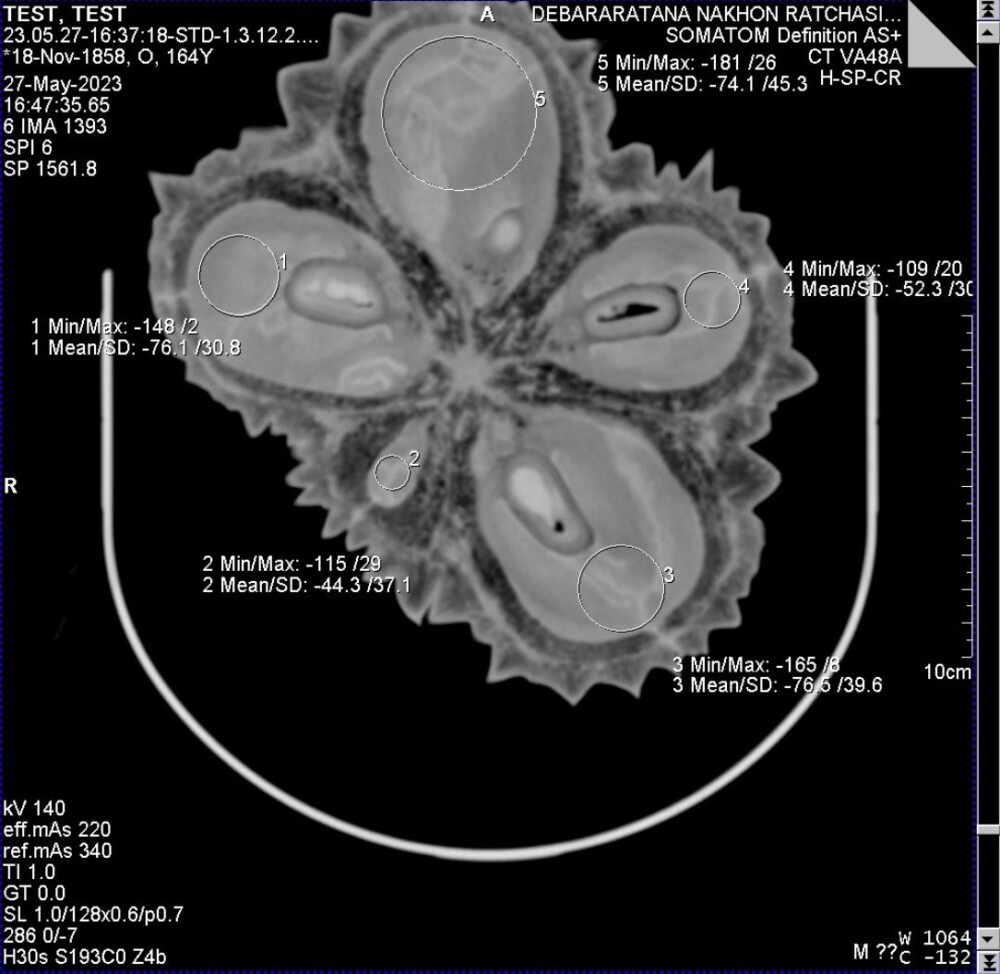

ทั้งนี้เครื่องจะสแกนภาพออกมาหลายเฟรม ในแต่ละเฟรมจะแสดงค่า CT-Numbers ที่บ่งบอกถึงความหนาแน่นของวัตถุ โดยการเปรียบเทียบกับความหนาแน่นของน้ำส่วนไหนที่มีความหนาแน่นมากกว่าน้ำภาพจะเป็นสีขาว ส่วนที่มีความหนาแน่นน้อยกว่าน้ำ เช่น อากาศ จะมีภาพเป็นสีดำ ซึ่งทุเรียนอ่อนจะมีน้ำเยอะกว่าทุเรียนแก่ โดยปัญหาการทดลองช่วงแรกพบว่า เมื่อเครื่องสแกนทุเรียนแล้ว ตัวสายพานรางเลื่อนผลทุเรียนจะย้อนกลับออกมาทางเดิม ซึ่งทางคณะผู้วิจัยได้มีการปรับแก้ไขให้รางเลื่อนผ่านไปทางเดียว ไม่ต้องย้อนกลับมาทางเดิมอีก เนื่องจากหากต้องนำไปต่อยอดเชิงพาณิชย์ที่มีผลผลิตจำนวนมากเครื่องต้องสามารถทำงานได้รวดเร็วและไม่ยุ่งยากซับซ้อน

อย่างไรก็ตาม ปัจจุบันเครื่องต้นแบบ CT-Scan สามารถสแกนผลทุเรียนออกมาเป็นภาพที่มีความละเอียดสูง ด้วยระยะห่าง 1 ซม./เฟรม หมายความว่าหากผลทุเรียนยาว 30 ซม. เมื่อผ่านเครื่องสแกนจะได้ภาพออกมา 30 เฟรม ในแต่ละเฟรมห่างกัน 1 ซม. ครอบคลุมพื้นที่ตลอดผล จากนั้นจะนำค่า CT-Numbers ที่ได้ในแต่ละเฟรมมาประมวลผลด้วย AI ซึ่งถูกเขียนและพัฒนาขึ้นใหม่โดยเฉพาะ ให้สามารถจำแนกลักษณะความสุกและตรวจหาหนอนภายในลูกทุเรียนได้อย่างแม่นยำ ซึ่งจะเป็นประโยชน์ต่อการคำนวณระยะเวลาขนส่งในการส่งออกให้กับเกษตรกรและผู้ประกอบการ